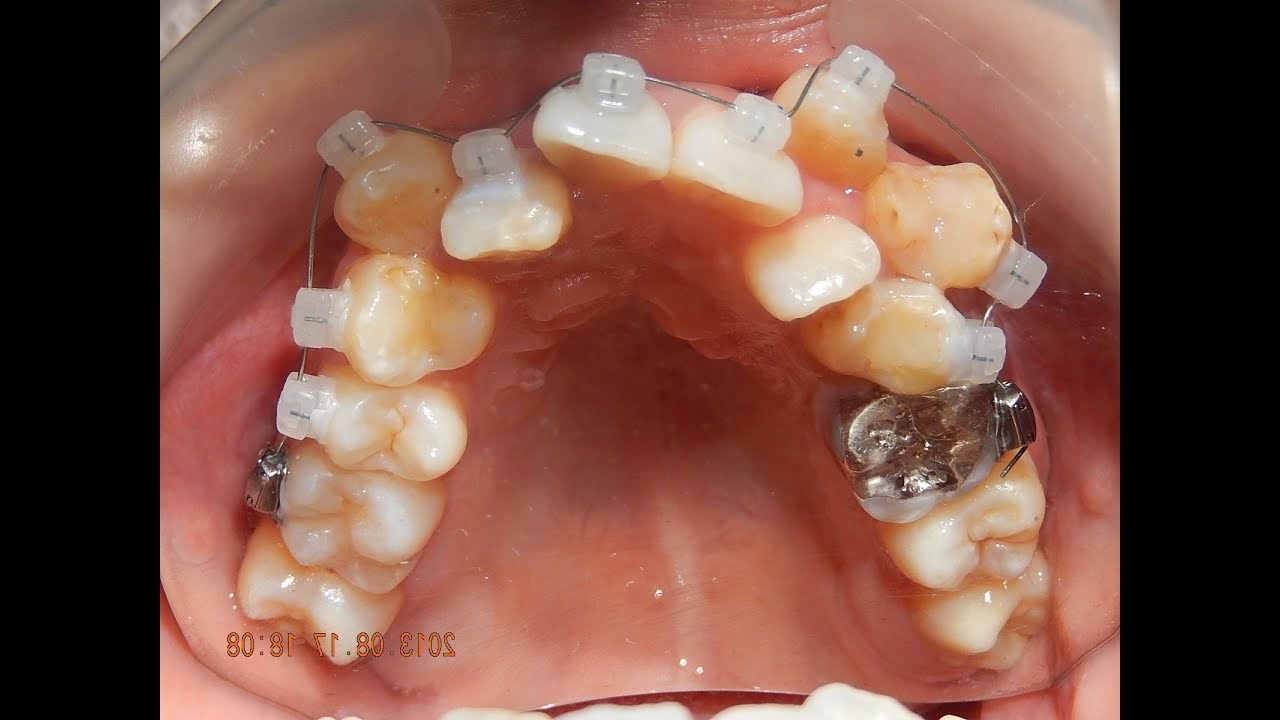

Ova osoba je imala katastrofalne zube. Fiksni aparatić za zube je to bez problema riješio. Princip je skroz jednostavan, a čini čuda. Pogledajte kako je ova "magija" napredovala i kako je izgledao krajnji rezultat nakon 4 godine.